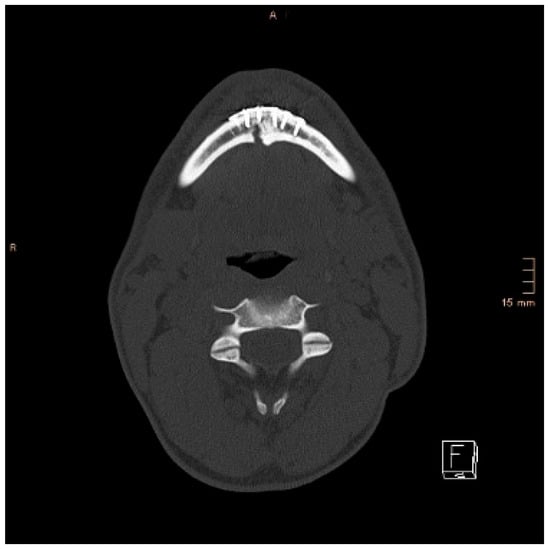

Figure 3. Axial CT scan with splaying of the lingual cortical bone in a symphyseal mandibular fracture after treatment with miniplates.

Figure 4. Axial CT scan showing the same patient as in Figure 3 after replacing the miniplates with a lag screw and considerable closure of the lingual gap. However, a small gap in the lingual cortical bone remained, and possibly determined a widening of the mandible.

Two operations had to be redone because of inadequate reposition in the symphysis/parasymphysis with broad (>2 mm) lingual splay. In both cases, straight miniplates were removed. Osteosynthesis was achieved with lag screws. Figure 3 depicts plate osteosynthesis of a symphyseal fracture with a broad lingual gap (Figure 3). Figure 4 shows the same patient after redo operation and osteosynthesis of the same fracture with a lag-screw and a marked reduction in the lingual splaying (Figure 4). Figure 5 demonstrates the condylar reduction in the frontal plane in the same patient. Figure 6 and Figure 7 show the patient’s occlusion (Figure 5, Figure 6 and Figure 7). The third redo operation was due to nonunion and infection of an angular fracture with fracture of the two condylar plates. In this case, after removal of the infected miniplate, the angle fracture was stabilized with a reconstruction plate and a miniplate from an extraoral approach; the two broken miniplates at the condylar process were left in situ.